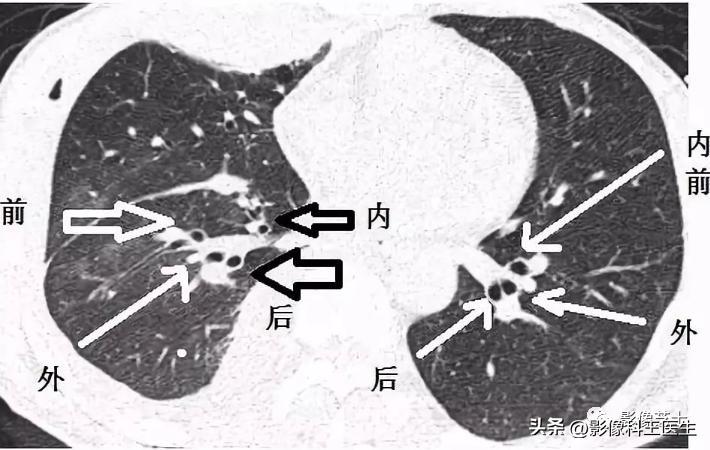

支气管分段

上叶支气管

尖段支气管 前段支气管 后段支气管